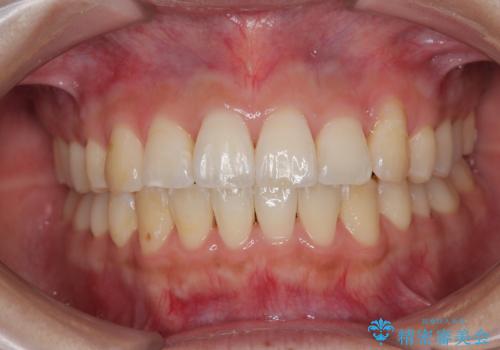

ワイヤー矯正と比較すると、八重歯が後方に傾斜した仕上がりとなりましたが、患者様ご希望のインビザラインにて十分な歯列を達成することができました。